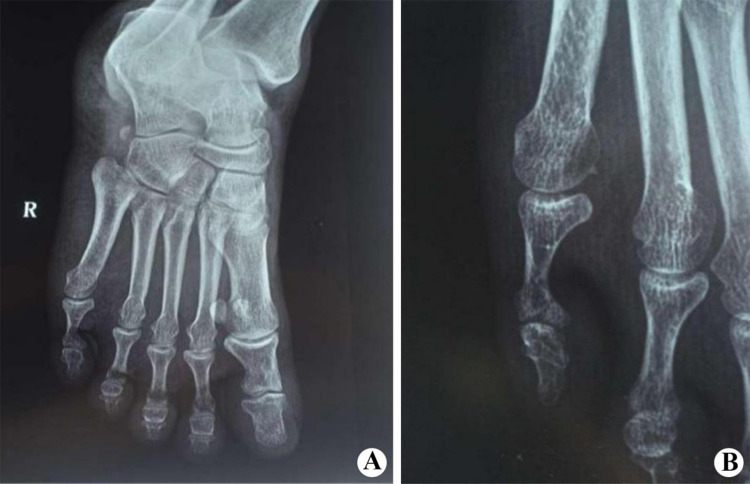

A 43-year-old man who had presented diffuse plaques on both hands and feet for 10 years and constriction of the fifth digit of the right foot for 1 year was included in this case report. Diffuse hyperplastic yellow-brown plaques were observed in the palms of both hands and soles of both feet in this man. Yellowish crusting formed on the plaques. There was much white debris on the surface lesions. The fifth phalanx of the right foot was ring-shaped and narrowed, and the toe was globular. Color Doppler ultrasound examination revealed arteriosclerosis and multiple small plaques in the right lower limb vessel. An antero-posterior radiograph of the right foot showed constriction of the fifth phalanx. The man was diagnosed with palmoplantar keratodermas complicated by pseudoainhum.

一例43岁男性,手脚弥漫性斑块10年,右脚第五指收缩1年。弥漫性增生性黄褐色斑块可见于该患者的手掌和脚底。斑块上形成淡黄色的硬壳。病灶表面有大量白色碎片。右脚的第五节指骨呈环状且狭窄,脚趾呈球形。彩色多普勒超声检查显示右下肢血管动脉硬化及多发小斑块。右脚前后位x光片显示第五指骨收缩。该男子被诊断为掌足底角化皮病并发假性风湿病。